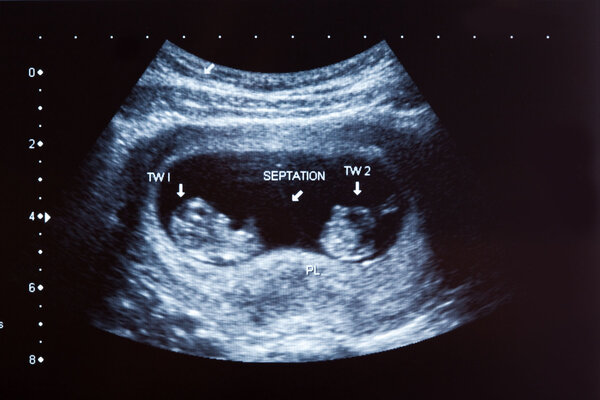

Für die medizinische Betreuung ist es entscheidend zu klären, ob die Föten eine gemeinsame Plazenta und/oder Fruchthülle teilen. Dies wird mithilfe von Ultraschalluntersuchungen beurteilt. Dabei liefert das sogenannte Lambda-Zeichen (λ) Hinweise auf eine dichoriale Mehrlingsschwangerschaft, während das T-Zeichen auf eine monochoriale Schwangerschaft hinweist.

Ob eine Mehrlingsschwangerschaft vorliegt, kann in der Regel ab der 7. Schwangerschaftswoche, also schon bei der ersten Ultraschalluntersuchung, festgestellt werden.